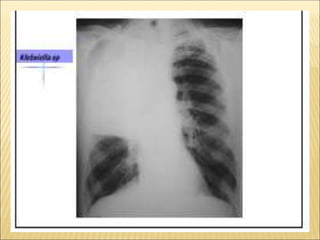

PNEUMONIA SEGMENTAR

PNEUMONIA EM CRIANÇAS

ETIOLOGIA

Crianças menores de cinco anos

Streptococcus pneumoniae

Haemophylus influenzae

Stafilococcus aureus

Crianças menores de dois meses

Bactérias gram-negativas (Klebsiela, E. coli)

Clamídia tracomatis

Crianças maiores de cinco anos

Micoplama pneumoniae

VÍRUS